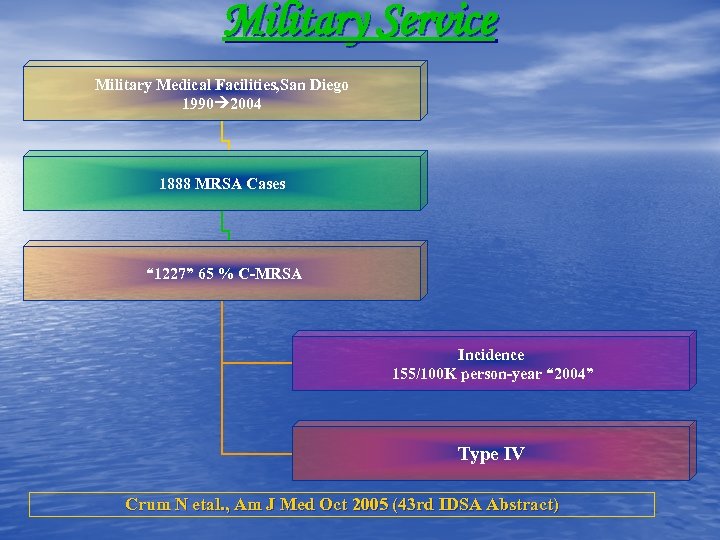

Military Service Military Medical Facilities, San Diego 1990 2004 1888 MRSA Cases “ 1227” 65 % C-MRSA Incidence 155/100 K person-year “ 2004” Type IV Crum N etal. , Am J Med Oct 2005 (43 rd IDSA Abstract)

Military Service Military Medical Facilities, San Diego 1990 2004 1888 MRSA Cases “ 1227” 65 % C-MRSA Incidence 155/100 K person-year “ 2004” Type IV Crum N etal. , Am J Med Oct 2005 (43 rd IDSA Abstract)